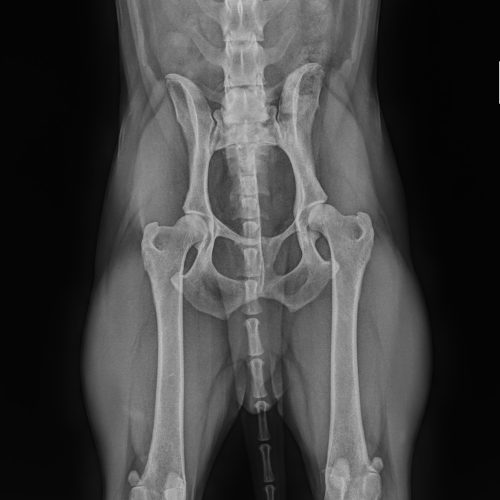

• röntgen vizsgálatok /diszplázia szűrés/

Diszplázia szűrés

Röntgen diagnosztika

Röntgen vizsgálatok